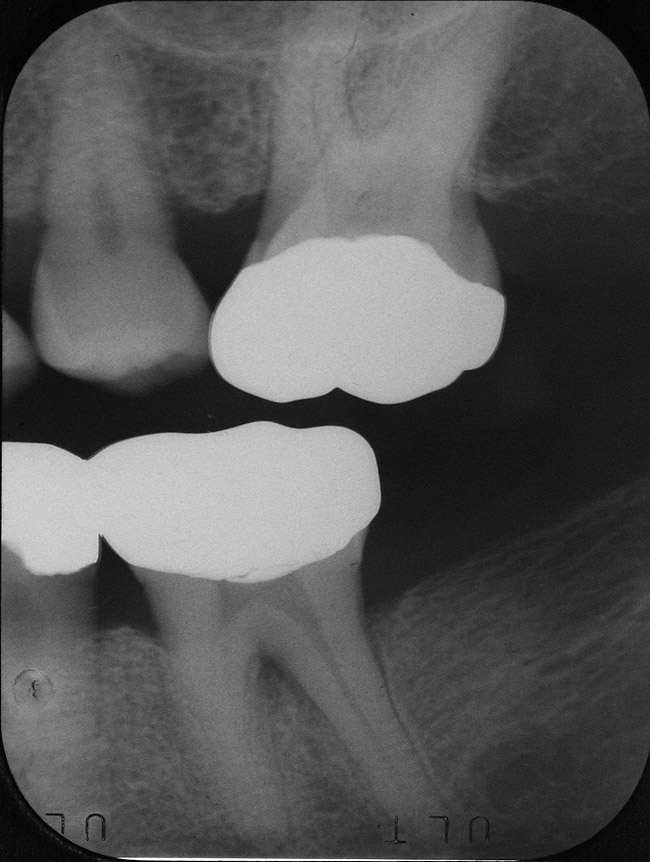

Inflammation limited to soft tissues around a dental implant may result from dental plaque colonization and is termed peri-implant mucositis. This is a reversible inflammatory condition limited to the soft tissues around the implant (without any bone loss), analogous to gingivitis around natural teeth. A diagnosis of peri-implantitis results when the inflammation spreads apically, causing progressive loss of osseointegrated supporting bone, analogous to periodontitis around natural teeth16 (Figure 2A and Figure 2B). It is essential for practitioners to be familiar with these diagnostic terms when assessing the long-term success of implants and peri-implant health (Table 1).

It is also important that the etiology and chronology of bone loss around implants be identified. Peri-implant bone loss resulting from surgical trauma or technique, such as pressure necrosis from inadequate osteotomy preparation or coronal bony voids from excessive countersinking, must be differentiated from peri-implant bone loss resultant from bacterial plaque-mediated immunoinflammatory bone loss. Implants placed using a subcrestal platform position tend to have deeper baseline probing depths than those placed supracrestally; therefore, it is important to know the baseline probing depth after initial healing to allow monitoring for changes over time.

Following implant restoration, patients should be reevaluated regularly (ie, every 3 to 4 months) during the first year. After the first year, the peri-implant-tissue response should be evaluated and then the required customized frequency of PM should be determined, as discussed earlier in this article. Initial bone loss during the first year can be expected to be near the level of the first thread or may be less in systems that include platform switching.43 Additional bone loss of approximately 0.1 mm per year for the first 5 years (up to a total of 1.5 mm) is considered normal.44 Complete seating of the associated parts (abutment and/or restoration), occlusal overloading, absence of restorative overhangs, and the removal of all restorative cements also should be verified from the radiograph because these problems can predispose to long-term complications.45

Figure 2a

Figureb 2  (A) Clinical and (B) radiographic views of implants at site Nos. 30 and 31 demonstrating bone loss caused by peri-implantitis after 8 years in function. Note gingival inflammation and plaque accumulation around implants.

Figure 2b